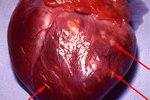

Myocarditis

apart from the other organs in our body heart has a special role to play. all the other organs deepend on heart for the supply of blood that’s why it is the most important organ. heart is covered by a special membrane which have certain functions is called myocardium. the swelling of myocardium due any reason is termed as myocarditis.

apart from the other organs in our body heart has a special role to play. all the other organs deepend on heart for the supply of blood that’s why it is the most important organ. heart is covered by a special membrane which have certain functions is called myocardium. the swelling of myocardium due any reason is termed as myocarditis.